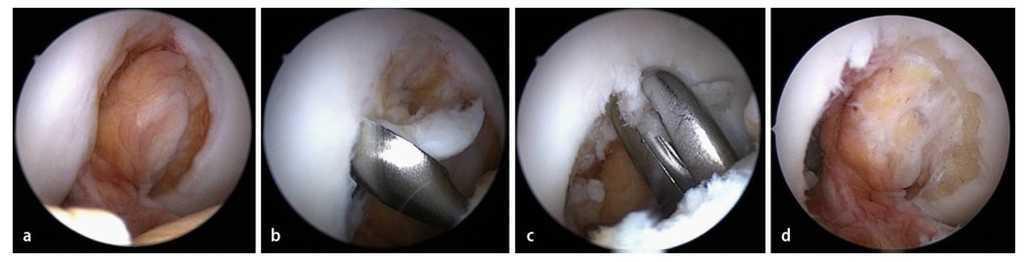

Fig. 2 Para la cirugía de reemplazo artroscópica del ligamento cruzado anterior son necesarios dos abordajes artroscópicos hacia la articulación de la rodilla. La extracción del tendón se realiza a través de una incisión oblicua de 3 cm de longitud aproximadamente, medial a la tuberosidad tibial (fig. 5). A través de este abordaje se realiza también la perforación del túnel tibial. El artroscopio se introduce a través de un portal anterolateral alto (A). El portal anterolateral alto ofrece un buen ángulo de visión sin que los cuerpos adiposos infrapatelares puedan desplazarse por delante del artroscopio. A través del portal medial (B) se realiza la preparación de la inserción femoral del LCA y se perfora también el túnel femoral. A través de un portal anteromedial alto (C) el proceso de perforación se puede controlar mediante artroscopia. Otras intervenciones adicionales en el menisco se pueden realizar a través del portal medial. En caso de que la accesibilidad del menisco sea difícil a través de este portal, serán necesarios otros abordajes (línea).